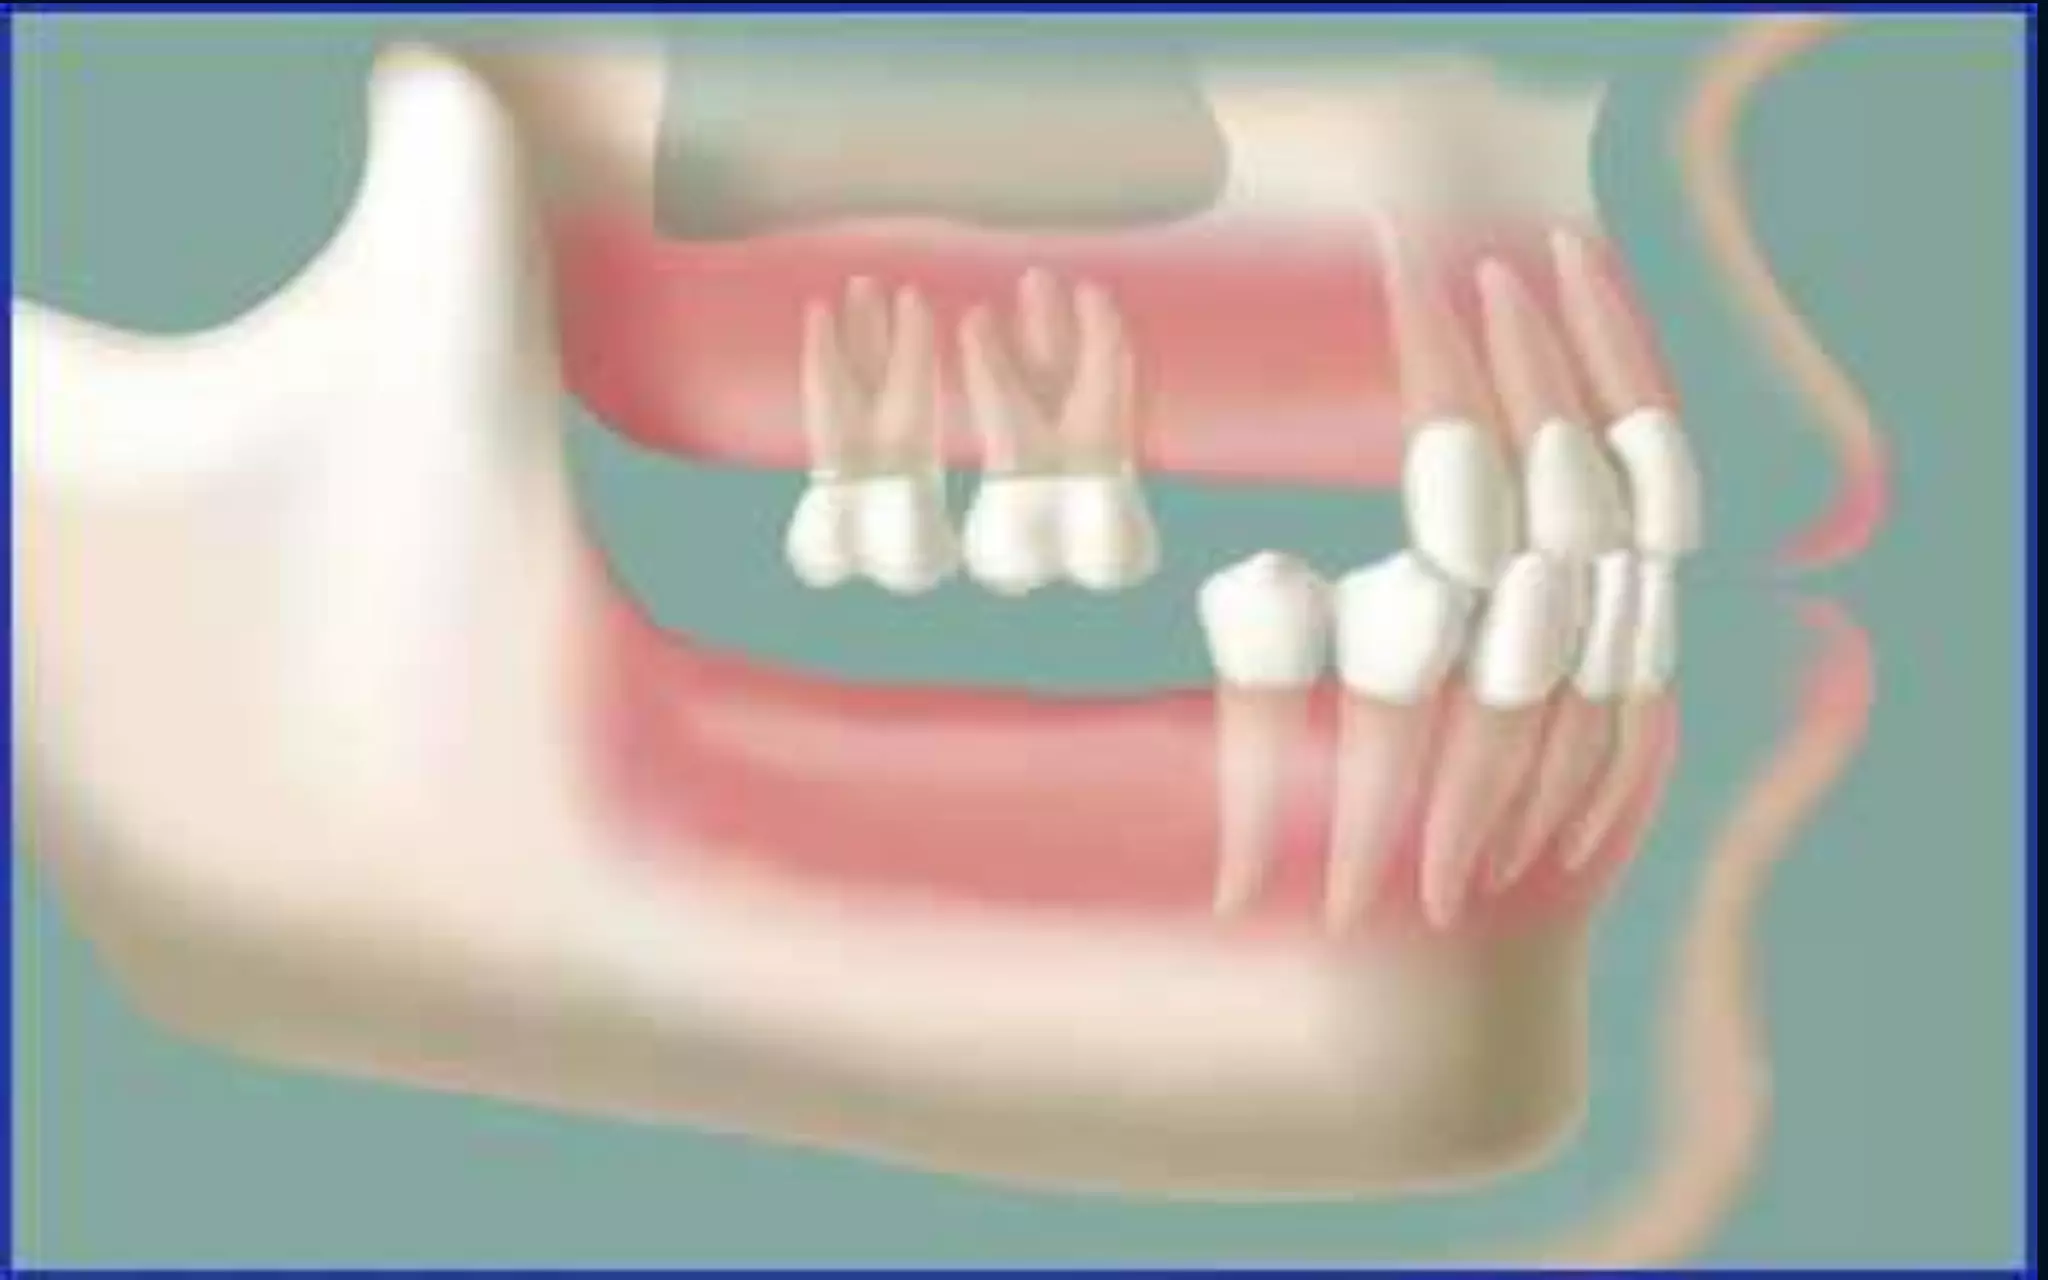

• Without the stimulation of the tooth or root the above

become unused &continuously resorbs.

•When a tooth is lost , the lack

of stimulation to the residual

bone causes a decrease in

trabeculae and bone density

in the area, with loss in

external width, the height, of

the bone volume

•With top premolars missing and

premolars have no opposing force

so they continue to erupt

•With no posterior contact all the

force is placed on anterior teeth

which in turn are overloaded and

pushed forward and outward

•Clinical example of side view

•2 lower molars missing

• Without the counter forces of the

bottom teeth , the top teeth supra

erupt

•Missing lower molar

•A single tooth loss in lower arch can

result in the tooth drifting forward

•This create poor contact and

periodontal (gum) problems

around the moving tooth